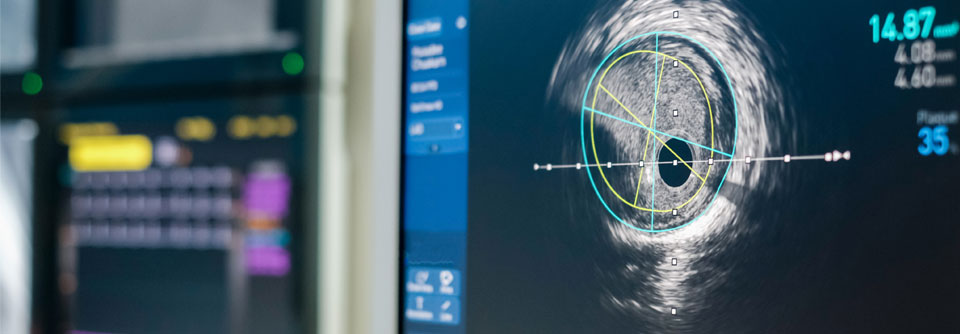

In einem Editorial bekräftigt Professor Dr. ­Mai ­Tone ­Lønnebakken von der Universität Bergen diese Einschätzung und weist ausdrücklich auf die Geschlechterproblematik hin: Ihrer Ansicht nach fehlen Risikomarker – genetische, metabolische, bildgebende und inflammatorische Parameter –, anhand derer insbesondere die Gefährdung von solchen Frauen, bei denen herkömmliche Risikofaktoren fehlen, abgeschätzt werden kann.